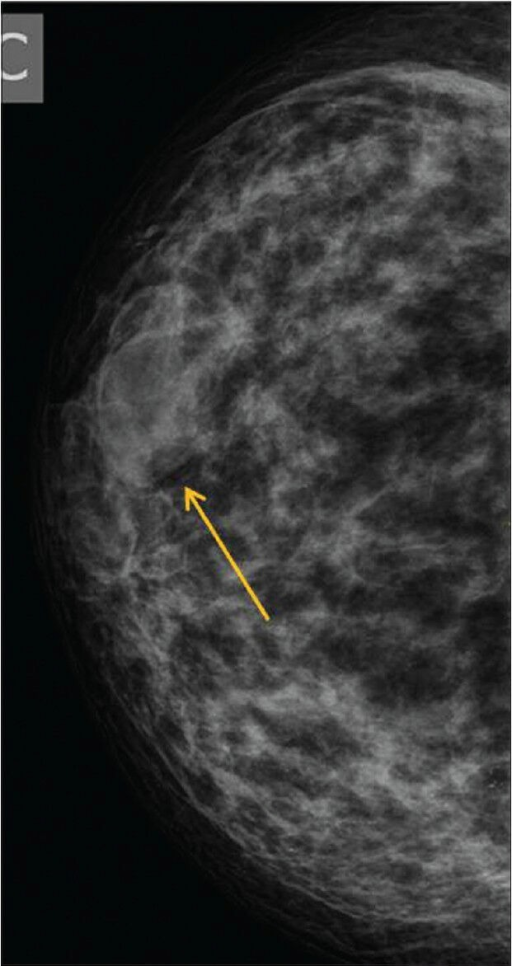

Radial Scar

Radial scars (complex sclerosing lesions) are hardened areas of breast tissue surrounded by abnormal ducts and tissue structures. Most radial scars are found on mammograms. As they resemble cancer, they require core biopsy for testing. Surgical excision is often recommended to confirm the surrounding tissue is normal. A referral to a breast surgeon is required for further investigation.

Pictorial essay: Breast USG by G. Shah and B. Jankharia is licensed under CC BY 2.0